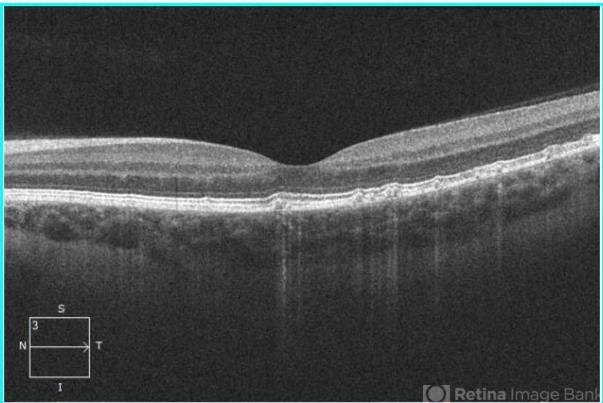

- drusen, optical coherence tomography (OCT), Bruch's membrane

- Alexandr Stepanov MD, PhD, FEBO, Faculty Hospital Hradec Kralove, Czech Republic

- Optical coherence tomography system

- Autosomal dominant drusen of Bruch's membrane, OCT.